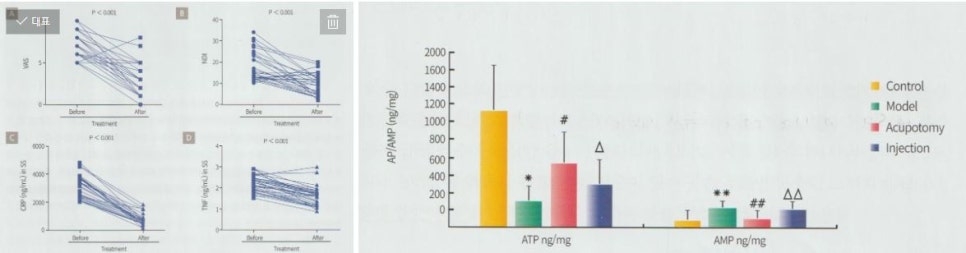

임상에서는 관리 전후로 통증 점수 변화를 비교하기도 합니다.

관리 이후에는 통증 점수가 감소하고 움직임이 보다 부드러워지는 변화를 보이는 경우가 있습니다. 또한 조직 순환이 개선되면서 근육 활동과 관련된 대사 환경이 변화하는 양상이 관찰되기도 합니다.